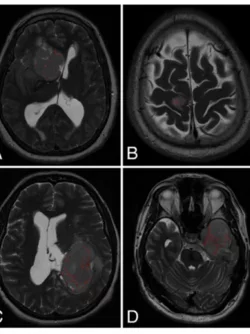

MVI Measured on axial T2-weighted MR images using the ITK-SNAP software.

Lagman, Carlito et al. "The meningioma vascularity index: a volumetric analysis of flow voids to predict intraoperative blood loss in nonembolized meningiomas." Journal of neurosurgery J30.5 (2018): 1547-1552